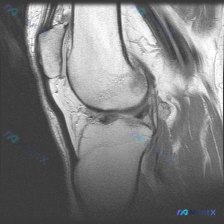

这是一份膝关节矢状位T1加权序列MRI,有人提出这份影像可以观察到「软骨异常」,我们先来看详细的影像分析结果:

- 骨骼结构:股骨远端、胫骨近端、髌骨骨皮质连续,无骨折;骨髓信号正常,无异常低信号提示水肿或占位;关节面软骨下骨板平整

- 半月板:前后角形态完整,信号均匀低信号,无明显内部信号增高提示退变或撕裂

- 韧带:前后交叉韧带走行连续,形态信号正常,无撕裂征象

- 肌腱:股四头肌腱、髌腱走行清晰,信号均匀,无附着点病变

- 关节与周围软组织:无明显关节腔积液,腘窝无囊肿占位,皮下软组织层次清晰

整个切面所有主要结构都保持了T1序列下的正常信号特征,未发现明确的病灶或异常信号区。

用户观察说有「软骨异常」,但这份T1序列的客观分析得出的结论是「未见明确结构性异常」,关节软骨下骨板还是平整的,也没有描述任何软骨形态或信号的异常,两者完全矛盾。